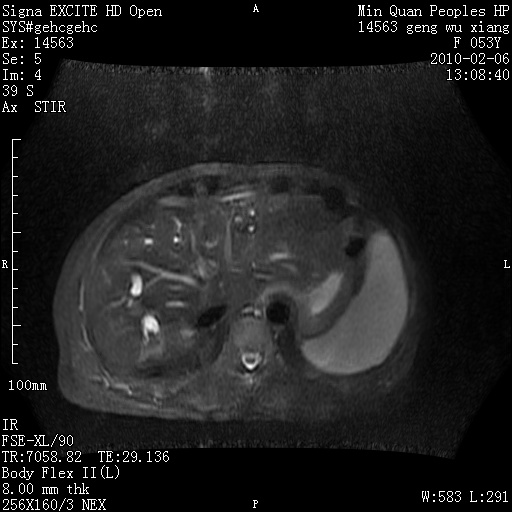

标题: MRI2762:胆道梗阻原因?

f,53y,全身黄染多日。

高位胆道梗阻 胆管癌可能性大

支持 高位胆道梗阻 胆管癌可能性大。